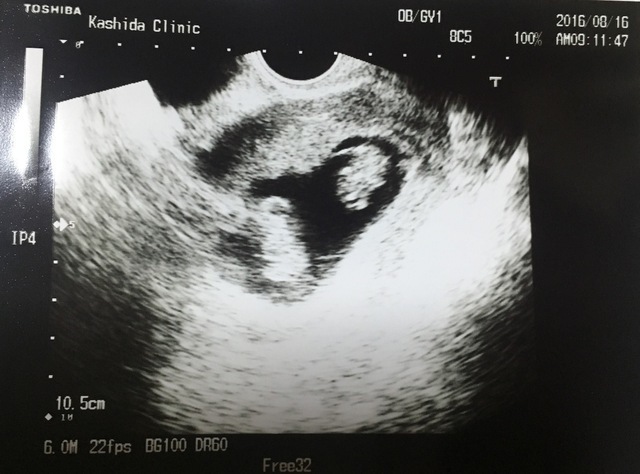

8週0日(8w0d・女の子)|akieeeen さん(26歳)

エコー写真撮影時のエピソード:

旦那が社員旅行に行っている時に送った写真です。検診に行ったらすぐに写真送ってって言われていたのですぐに送りました。

社員旅行中ですがエコー写真を見るなり電話してテンション上がっていたのを覚えています。電話ごしから赤ちゃんに声をかけていました。